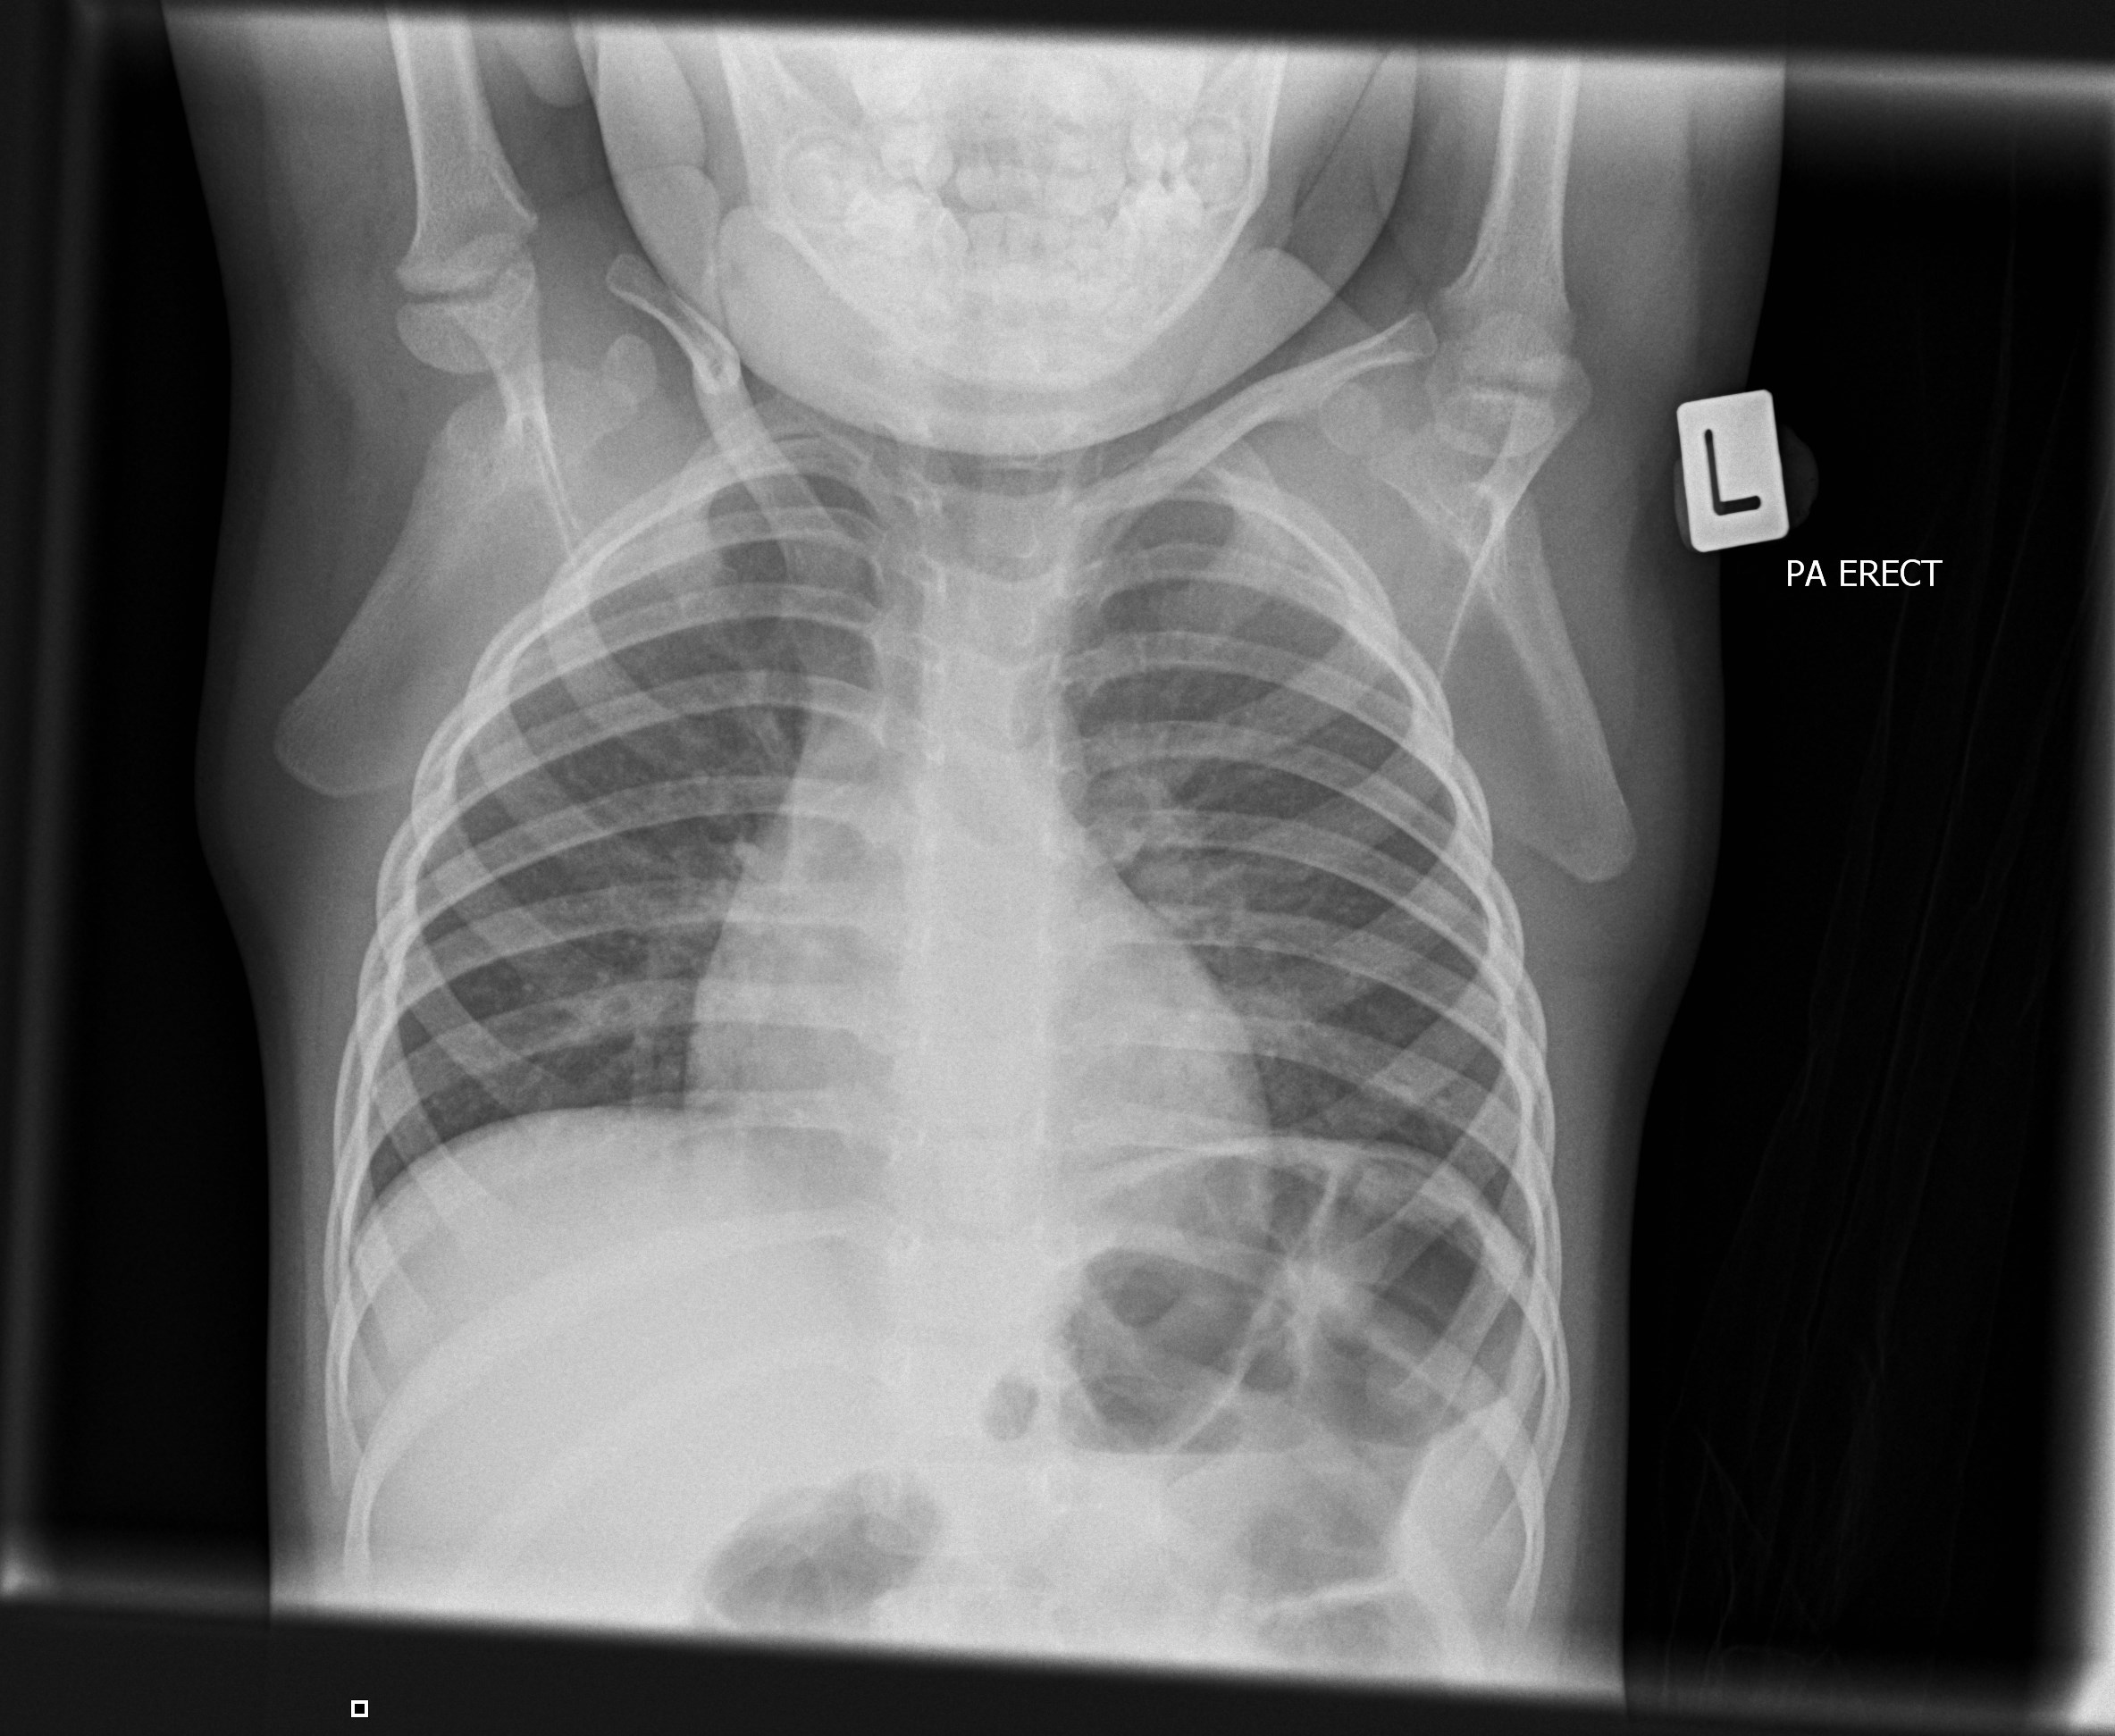

frontal view of normal pediatric chest xray Stock Photo Alamy Chest X Ray Pediatric Normal The lateral chest view examines the lungs, bony thoracic cavity, mediastinum, and great vessels. Initial chest radiograph obtained immediately after surgery (a) shows normal contour of superior mediastinum. Radiographic imaging of the pediatric chest presents several unique challenges and nuances, stemming from congenital variants and pathologic. Normal anatomy and artefacts the anteroposterior (ap) diameter of the neonatal chest is almost. Chest X Ray Pediatric Normal.

Chest X Ray Pediatric Normal . Initial chest radiograph obtained immediately after surgery (a) shows normal contour of superior mediastinum. The lateral chest view examines the lungs, bony thoracic cavity, mediastinum, and great vessels. This article lists examples of normal imaging of the pediatric patients divided by region, modality, and age. Radiographic imaging of the pediatric chest presents several unique challenges and nuances, stemming from congenital variants and pathologic. Normal anatomy and artefacts the anteroposterior (ap) diameter of the neonatal chest is almost as great as its transverse diameter,.